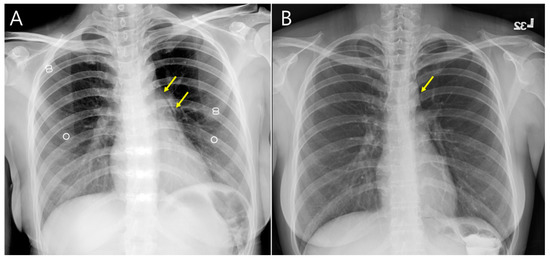

Point-of-Care Ultrasonography Helped to Rapidly Detect Pneumomediastinum in a Vomiting Female

2. Case Presentation